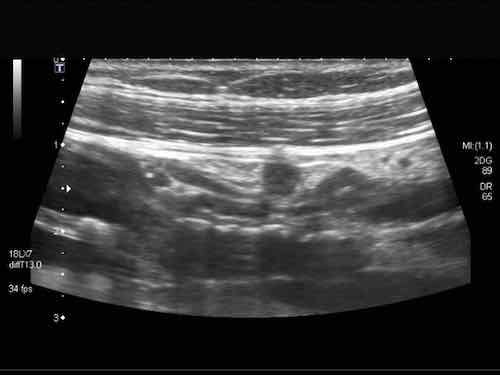

Đây là hình ảnh của hồi tràng tận cùng ở ba trẻ em và người trẻ tuổi khác nhau với các mảng Peyer lớn biểu hiện dưới dạng dày lớp niêm mạc sâu không đối xứng, giảm âm.